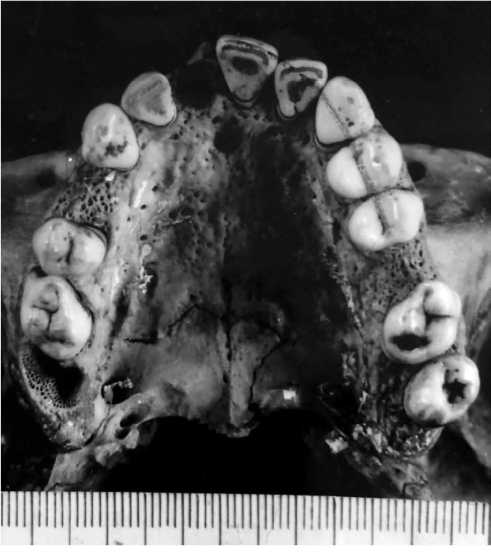

The study revealed the following: the skull was of medium size (Fig. 1) and brachycranial shape (cranial index 87.5%); morphological and metric parameters indicated the male sex; morphological features of the studied bones indicated the age of 30–39 years. The age was established using the methods of Zvyagin (1975) [4] and Acsady Nemeskeri in the edition of Sjøvol (1975) [5]; when determining the race of the skull, the method of Zvyagin (1981) was used [6]. The studied skull belonged to the mixed racial group (among the identifying features of the skull there were eight presumably Caucasian indicators, 12 presumably Asian indicators, the rest of the indicators are undetermined). Examination of the teeth revealed shovel-shaped incisors on the upper jaw, torsion and inward displacement of the second upper incisor (Fig. 2). In addition, enamel leaks were found on the first and second large molars of the lower jaw (Fig. 3).

Fig. 1. Skull submitted for examination.